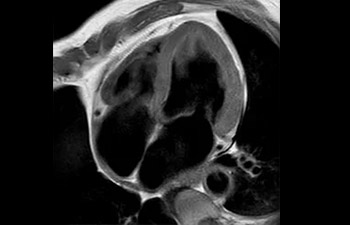

• Es una innovadora técnica de aceleración que no solo permite agilizar las secuencias, sino todo el estudio. • Implementación especial con la que las exploraciones en 2D y 3D pueden llegar a ser hasta un 50% más rápidas con una calidad de imagen prácticamente equivalente.1

• Se puede usar con todos los contrastes y con todas las regiones anatomías.

con Compressed SENSE